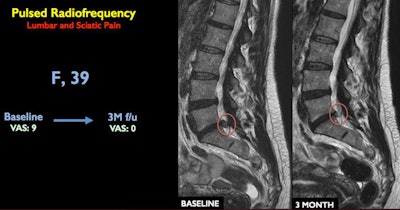

Napoli and colleagues conducted a prospective study that included 80 patients who had been experiencing back pain for at least three months due to a herniated disk that did not respond to more conservative therapy, such as exercise and medication.

Under CT guidance, interventional radiologists inserted a needle at the location of the bulging disk and nerve root. The clinicians then inserted a probe through the tip of the needle that delivered pulsed radiofrequency (RF) energy to the problem area over a 10-minute period. The RF energy resolves the herniation without touching the disk, Napoli reported.

Of the 80 patients who received a single 10-minute treatment, 81% reported they were pain-free after a year. Six patients needed a second pulsed RF session, and 90% of the patients were able to avoid open surgery.